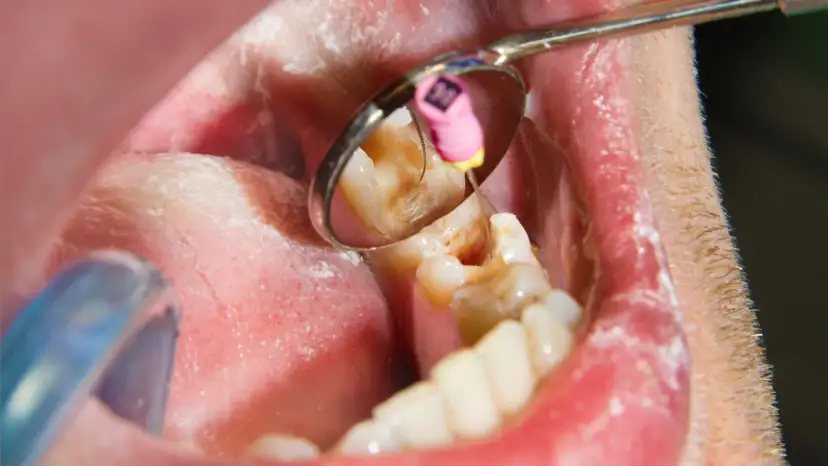

Torbiel pod zębem - dowiedz się, czym jest, jakie daje objawy i powikłania. Sprawdź, kiedy boli, jak diagnozować i leczyć, by uniknąć zagrożeń. Czytaj!